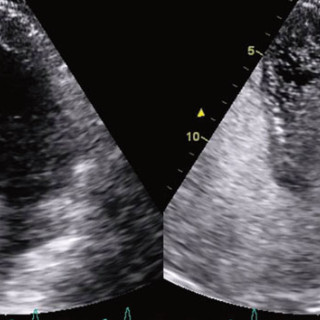

Sentrale venekatetre brukes rutinemessig i pasientbehandlingen ved norske sykehus. Den sentralvenøse tilgangen oppnås gjennom punksjon av v. jugularis interna, v. subclavia eller v. femoralis. Komplikasjoner knyttet til bruken ses både i forbindelse med selve innleggingen av kateteret, når kateteret er på plass og i bruk og når det skal fjernes. Komplikasjoner knyttet til innlegging av et sentralvenøst kateter er punksjon av nærliggende arterie, pneumothorax, arytmier, skade av plexus brachialis, skade på ductus thoracicus, luftembolisering og feilposisjonering av kateteret (1, 2)...